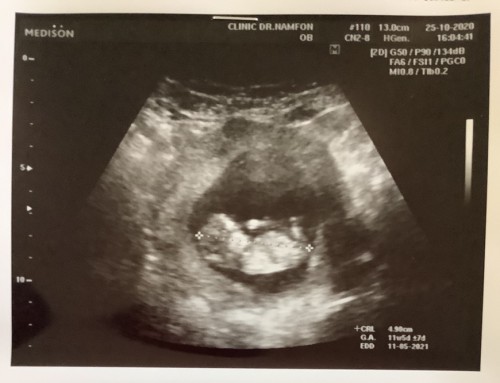

สวัสดีครับคุณพ่อคุณแม่ทุกท่าน ผมมีประสบการณ์ดีๆจะมาแชร์สำหรับคุณพ่อคุณแม่ในวัย40อัพที่อยากจะมีบุตรผมกับภรรยาอายุ41กันแล้ว เรา2คนพยายามจะมีบุตรมาเป็นระยะเวลาเกือบๆ7ปี เราได้ไปทำIUIมาแล้ว3ครั้ง แต่ก็ไม่ประสบผลสำเร็จ คุณหมอแนะนำให้ทำกิ๊ฟ แต่เนื่องจากค่าใช้จ่ายค่อนข้างสูงและเราทั้ง2ก็ต้องทำงานประจำและจังหวัดที่เราอาศัยอยู่ไม่มีรพ.ไหนรับทำกิ๊ฟ ต้องเดินทางไปจังหวัดใหญ่หรือไม่ก็กรุงเทพ เราจึงตัดสินใจรอกันต่อไป ผ่านมา4ปีจนอายุเข้า41เราเลยคิดกันว่าถ้าปีนี้ไม่มีก็คงจะไม่เอาลูกล่ะ พอมาต้นปี63น้องก็มา เราดีใจมาก ครรภ์ผ่านมา8สัปดาห์ปรากฎว่าน้องไม่สมบูรณ์ น้องไม่มีหัวใจ และแล้วสิ่งที่เราไม่อยากให้เกิดก็เกิดขึ้น น้องหลุดออกมาตอนสัปดาห์ที่10 เราเสียใจมาก จนรู้สึกท้อไปเลย แต่ก็ยังมีความหวังอยู่ เราใช้เวลาทำใจกันอยู่หลายเดือน จนในที่สุดกลางปี63 เราก็มีความหวังขึ้นมาอีกครั้ง น้องกลับมาแล้ว และครั้งนี้น้องแข็งแรงดีในครรภ์12สัปดาห์ อยากจะเป็นกำลังใจให้คุณพ่อคุณแม่ที่อยากจะมีลูก อย่าเพิ่งท้อและอยู่ด้วยความหวัง #ลูกคนแรก